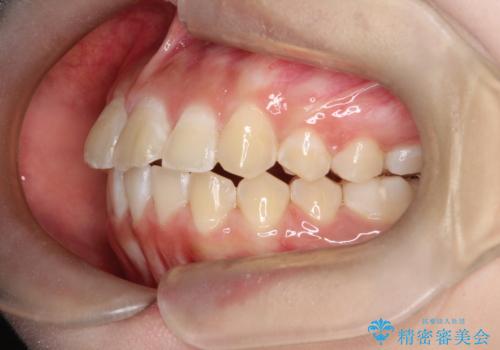

- 前歯が出ていることを主訴に来院されました。

インビザラインにて奥歯の遠心移動を行いながら最大限前歯が下がるように治療を行いました。

今回は遠心移動とIPRによってここまで前歯を下げることができました。